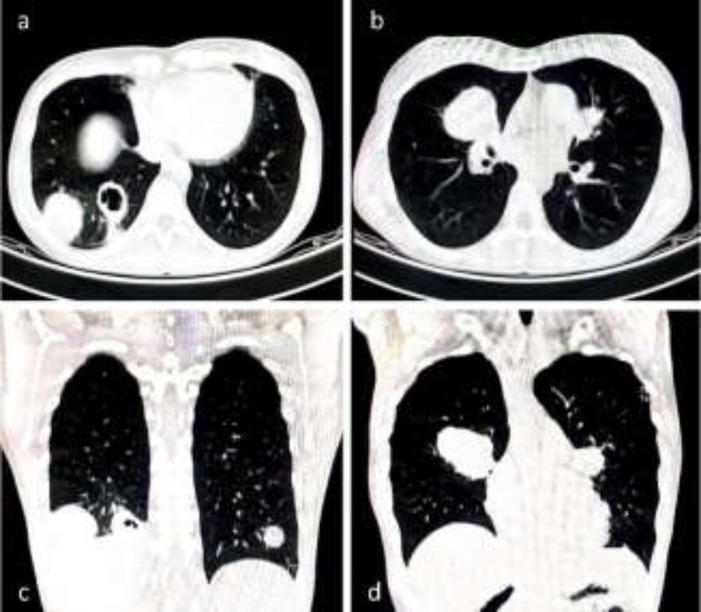

Hydatidosis is one of the most critical worldwide parasitic zoonotic diseases. The lung is the second most common site of hydatidosis. This study aimed to evaluate the clinical status, diagnosis, treatment, and radiological findings of pulmonary hydatid cyst in patients referred to tertiary lung center.

Pulmonary hydatidosis was confirmed for 234 patients. 55% of patients were males with the mean age of 45.1±16.6 years. The most common symptoms were cough (59.8%), dyspnea (31.1%), and hemoptysis (26%). Left lung, right lung, and bilateral involvement were reported in 40.1%, 55.1%, and 4.8% of cases, respectively. Cyst perforation (39.8%) was the most common intra-operative finding. Surgical interventions included thoracotomy, rigid bronchoscopy, cyst aspiration, and enucleation. The liver was the most concomitant organ involved due to pulmonary hydatidosis (16.6%). The most common postoperative complication was atelectasis, with the rate of 35.7%. 52.2% of patients were discharged within 10 days after surgery. No mortality was reported.

Sometimes atypical findings in different imaging modalities make the hydatid cyst diagnosis challenging. Although lobe involvement more than 50% has the indication for lobectomy, we conserved lobes with about 70% involvement in our institution, and patients had no postoperative complications.